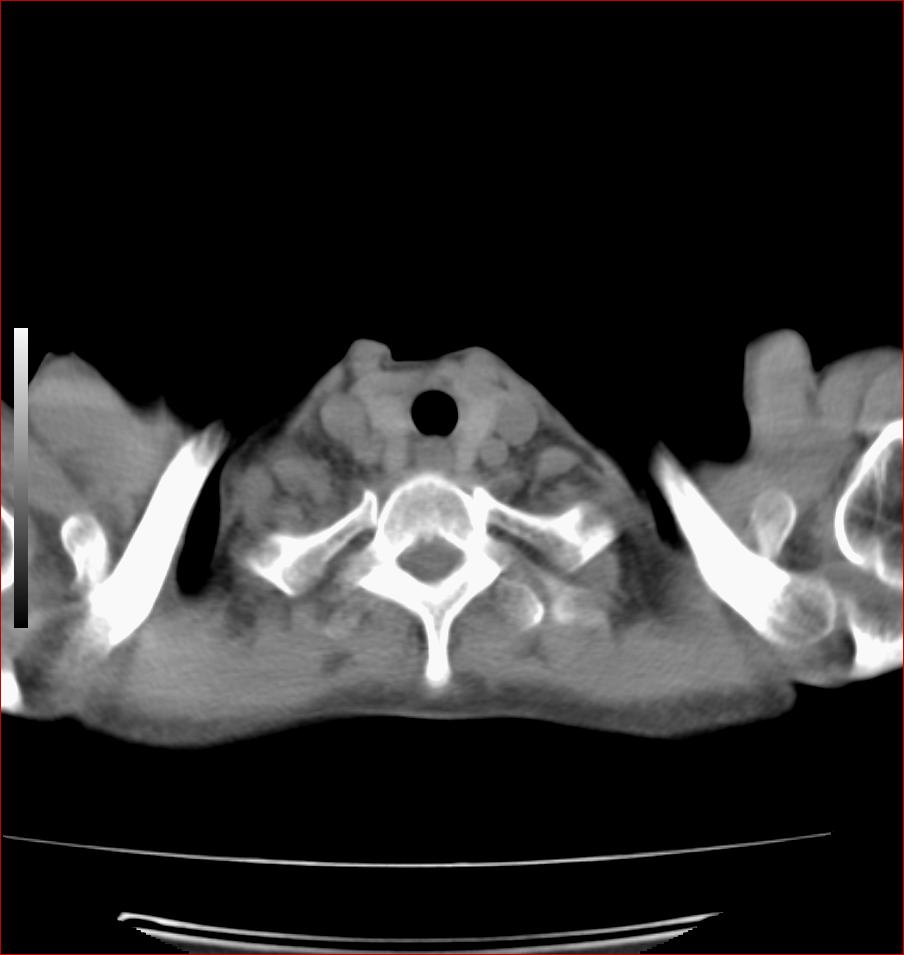

标题: CT17110:F56Y,纵隔囊肿;胸腺?淋巴?请各位老师看看 [打印本页]

女性患者 56 咽痛伴声嘶10+天入院。

右上纵隔囊性占位性病变;考虑支气管囊肿可能。

病变紧贴气管右壁,两者相互压迫,考虑支气管囊肿!

见相互挤压征,考虑气管囊肿,建议ct增强扫描